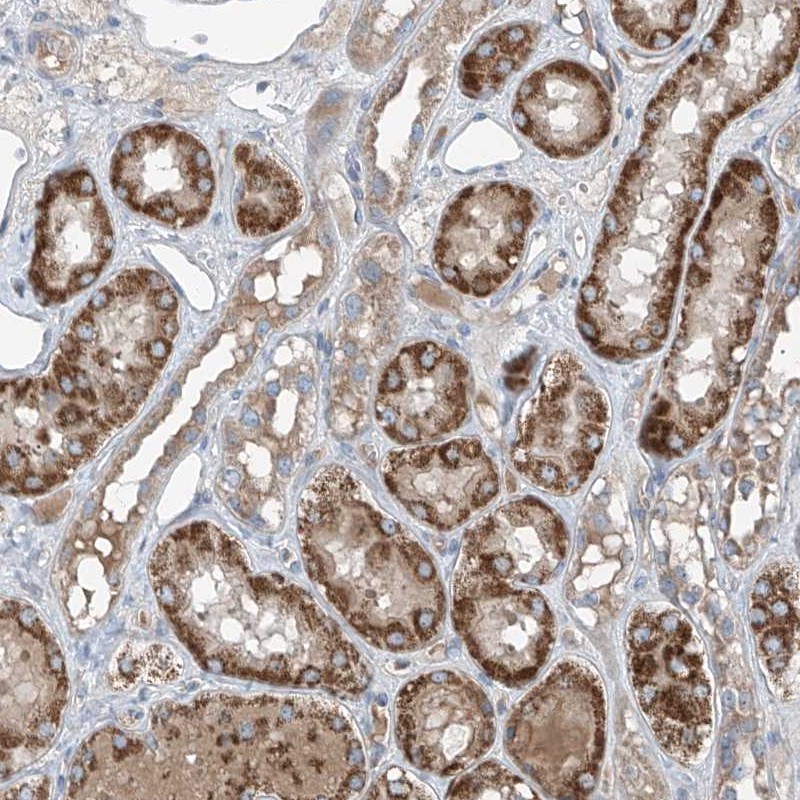

Immunohistochemical staining of human kidney shows strong cytoplasmic positivity in renal tubules.